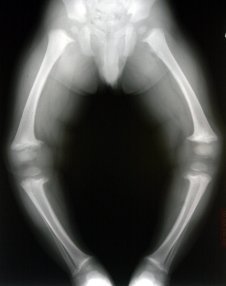

تقوس الساقين يمكن ان يكون طبيعي ويروح بعد عمر 1 سنة

او ممكن يكون علامة لنقص الكالسيوم وفيتامين د

وشوفي صورة التقوس الي مو طبيعي